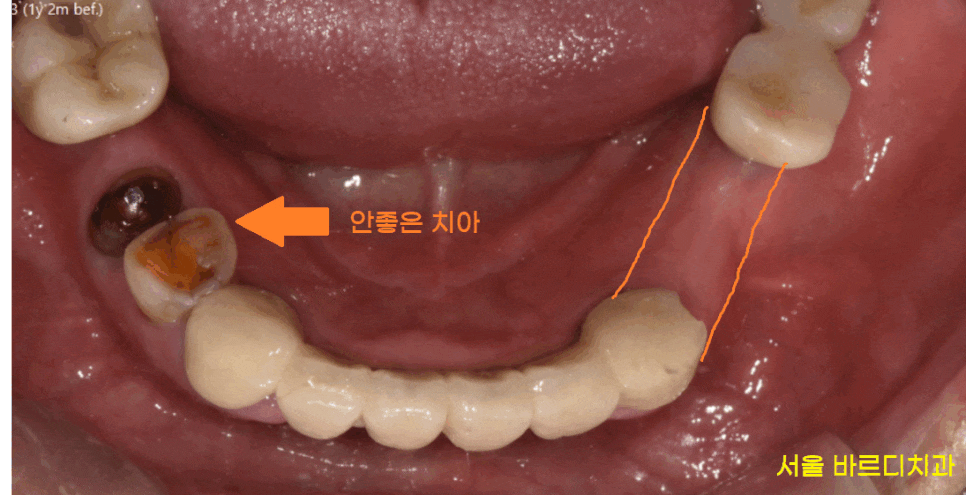

식사를 할 수 있는

어금니가 여러군데 빠진채로 내원해주신 환자분입니다.

치아 개수가 빠진게 많다보니

그러려니~ 하고

사셨다고 하네요ㅠㅠ

23.06.13

오른쪽 왼쪽 각각 1개 치아만

물리고 있는 상황이라

더이상은 버티시기 힘드셨대요

자연 치아 중에서도

많이 닳고 좋지는 않았지만

워낙 상실된 치아가 많아서

문제가 생기면 하나씩 치료하기로

상담해드리고..